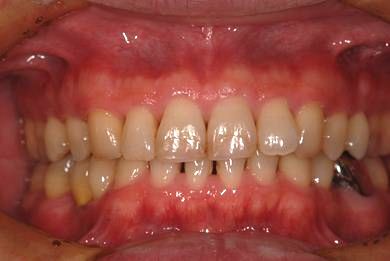

| 性別/年齢 | 男性 / 37歳 | ||||||||||||||||||||||||||||||||

| 主訴 | 前歯(2本)の欠けの治療 | ||||||||||||||||||||||||||||||||

| 治療方針 | 右下欠損部分をインプラント治療にて、機能的・審美的回復を行う。 | ||||||||||||||||||||||||||||||||

| 治療内容 | インプラント1本、メタルボンドセラミッククラウン1本 | ||||||||||||||||||||||||||||||||

| 総治療費 | 252,000円 | ||||||||||||||||||||||||||||||||

| 治療期間 | 7ヶ月 |